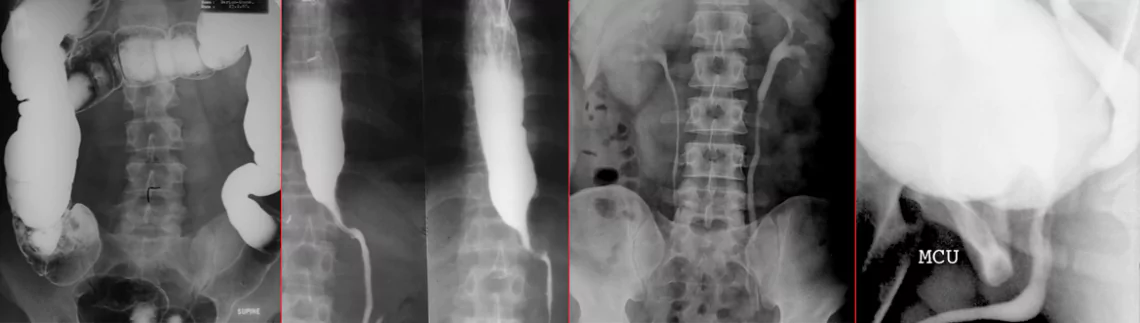

A. Barium Studies : Using barium, an inert substance, different parts of the gastrointestinal tract are studied.We have been the pioneers in developing the use of enteroclysis for evaluation of the small bowel.

Barium swallow for the esophagus requires no preparation. Barium meal for the stomach only needs six hours fasting and abstinence from smoking. Barium enema, follow-through and enteroclysis need a more detailed abdominal preparation, which will be explained in detail when giving the appointment.

10-20 minutes for barium swallow and meal. 1-2 hours for follow-through. 20-45 mins for enteroclysis and barium enema.

B. Intravenous Urogram/Pyelogram (IVU), Micturating Cystourethrogram (MCU), Sialogram, Sinusogram, etc. These require the use of iodinated contrast media